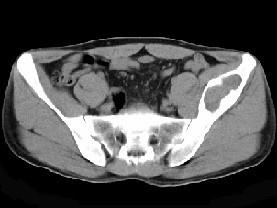

问题 男,34岁,左髂骨疼痛,有皮肤色素沉着,性早熟等,请结合所提供图像,选择最佳答案 ( )

选项 A、内生软骨瘤 B、骨巨细胞瘤 C、畸形性骨炎 D、骨纤维结构不良 E、非骨化性纤维瘤

答案 D